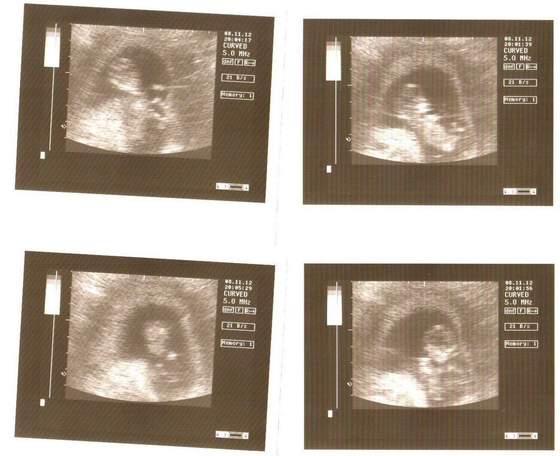

Wychodzi 13t2dz., maluszek ma lekko ponad 7cm, serducho 161x/min, NT 1,8, kość nosowa obecna, przepływy w normie, serducho i mózg prawidłowo.. ręce i nóżki obecne i wierzgające